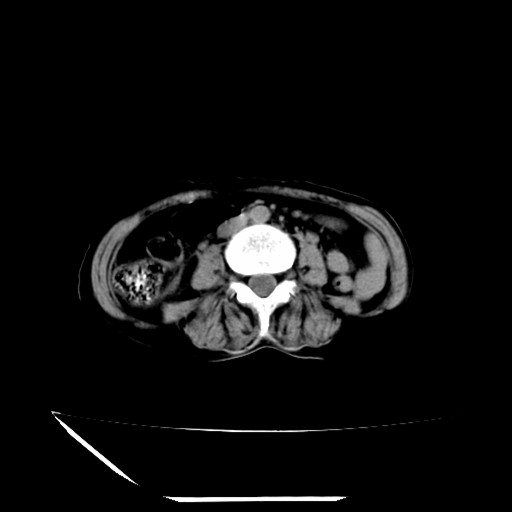

标题: CT16840:女-63岁,下腹部疼痛, [打印本页]

标题: CT16840:女-63岁,下腹部疼痛,

补充资料:血象是13.5,临床拟诊阑尾炎

本人诊断是右肾周围炎,阑尾炎,盆腔少许积液!

诊断右肾周围炎是因为我图像没有发完,诊断阑尾炎是因为相当于阑尾区连续两个层面可以看到增粗的阑尾显影。

支持阑尾炎!局部腹膜增厚,脂肪密度增高。应该手术治疗。